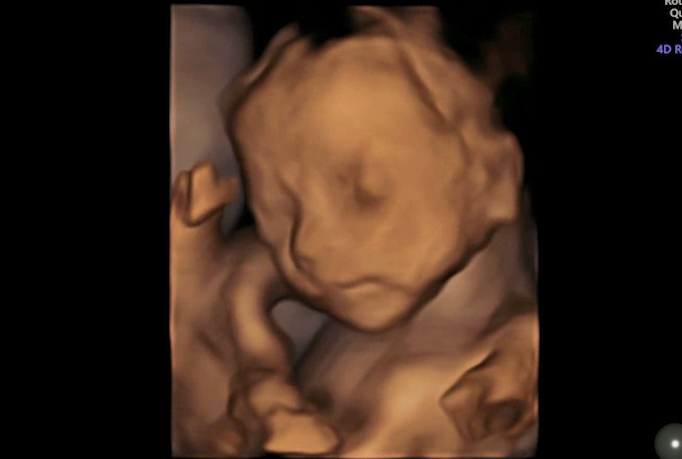

看到了宝宝的小模样

有部分宝妈还提前感受到了小宝宝的顽皮